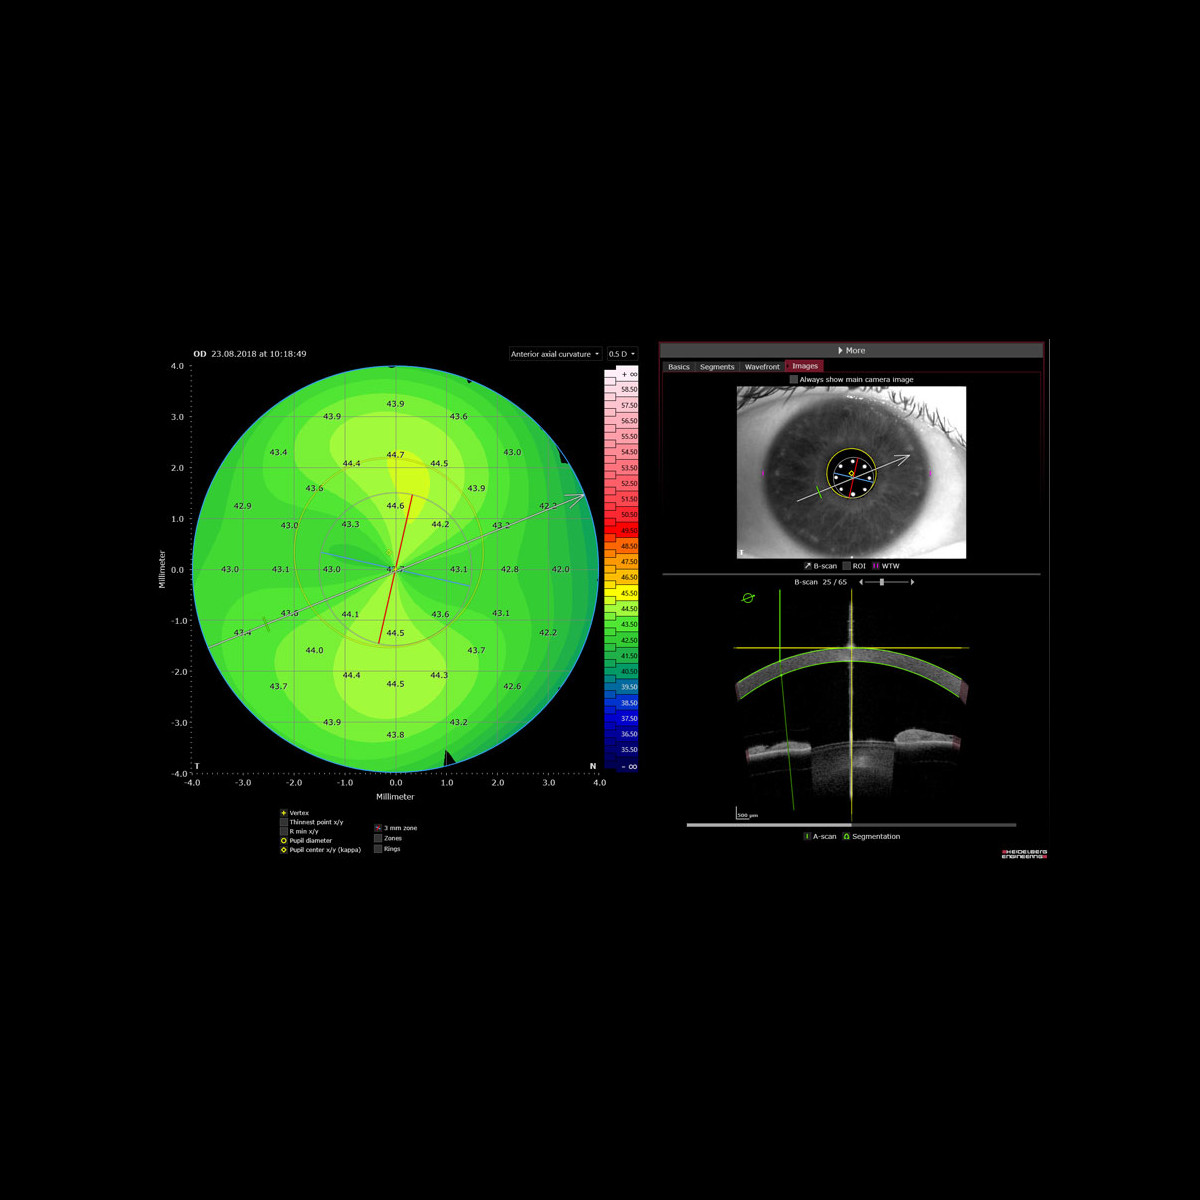

Als unverzichtbares Werkzeug für die Planung von Kataraktoperationen ermittelt ANTERION präzise biometrische Streckenmessungen sowie die gesamte Hornhautstärke, alles mit optimierter OCT-Technologie. So können Sie Ihre klinischen Ergebnisse selbst in den schwierigsten Fällen verbessern. Die OCT-Bilder helfen Ihnen dabei, Ihre Messungen zu bestätigen, sodass weniger Annahmen erforderlich sind.

Die Cataract App bietet sphärische und torische IOL-Berechnungen sowie Raytracing-Anwendungen und liefert die erforderlichen Daten zur Berechnung der für Ihre Patient:innen am besten geeigneten IOL, ohne dass Daten übertragen oder Geräte gewechselt werden müssen.